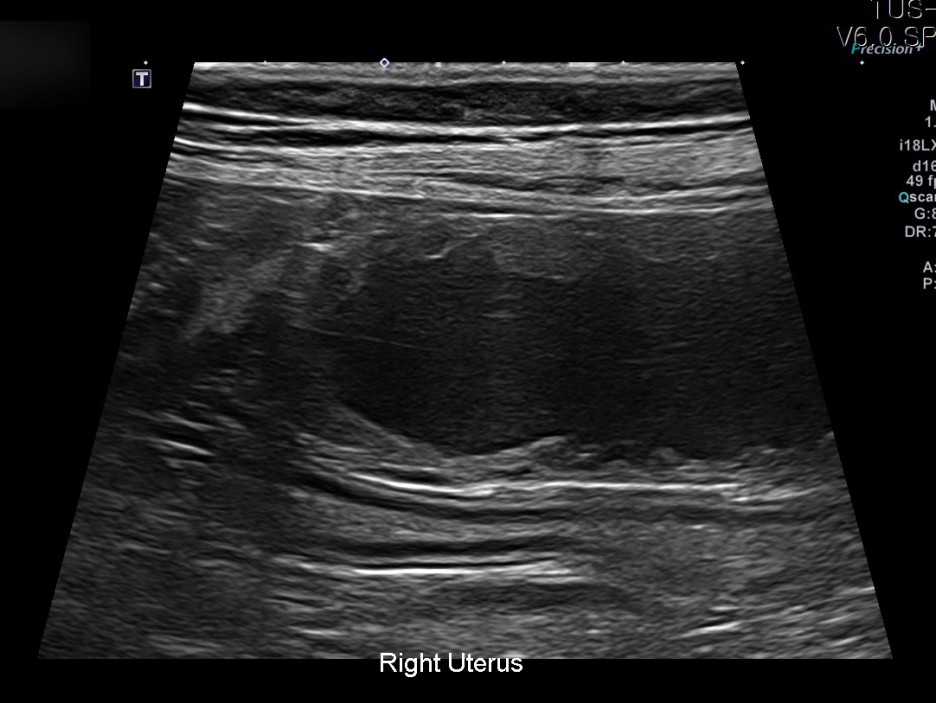

이어 진행된 초음파 검사에서는 자궁축농증으로 인해 내막이 두꺼워지고 크기가 커지는 염증성 변화가 진행되고 있었습니다.

✔US 양 자궁내막증식, 자궁각내삼출물에 의한 심한 확장소견